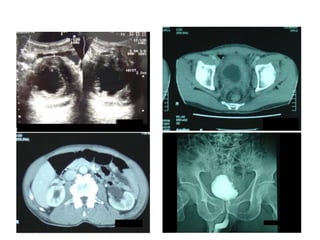

Больной Л., 64 лет, отметил примесь крови в моче в 1999 г. Установлен диагноз: Опухоль мочевого

пузыря. В последующие 23 месяца больному проводилась консервативная гемостатическая и

антибактериальная терапия под наблюдением участкового терапевта и хирурга.

С учетом неэффективности проводимого лечения, в 2001 г. пациент направлен в ЛПУ экспертного

уровня, где заболевание морфологически верифицировано при ТУРМП-биопсии, установлен

диагноз: РМП mрT3aN0M0G2.

Цистоскопия + МСКТ органов малого таза: по левой боковой стенке мочевого пузыря

безворсинчатая опухоль, до 7 см в диаметре, прорастающая за пределы стенки мочевого пузыря.

Дополнительно, по правой боковой стенке мочевого пузыря – небольшие, до 1 см опухоли на

нешироком основании. С учетом запущенности опухолевого процесса и отказа больного от

радикальной операции, РЦЭ не выполнена.

Август 2001 г. - выполнена ангиография сосудов мочевого пузыря. С октября 2001 г. по февраль

2002 г. проведено VI курсов регионарной ПХТ. По результатам КТ органов малого таза (2002) -

полная ремиссия опухоли, подтвержденная результатами ТУРМП-биопсии.

Через 14 месяцев - ТУРМП по поводу поверхностных рецидивов РМП, в дальнейшем признаков

продолженного опухолевого роста не отмечено.

Пациент жив 15 лет.

Октябрь 2001 г. Февраль 2002 г.